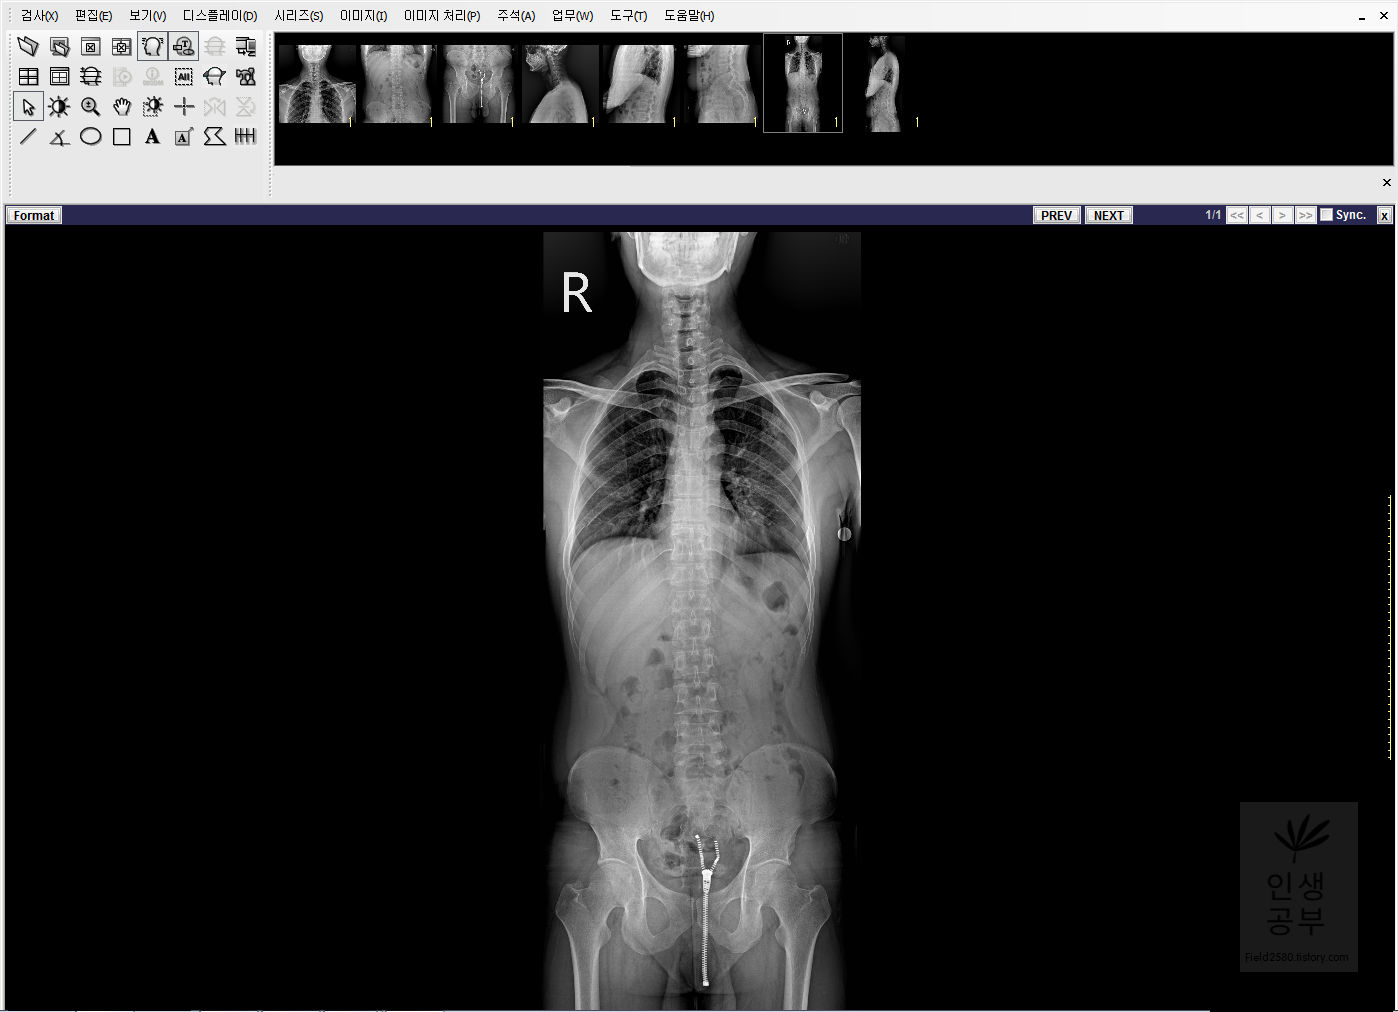

1. Display Workstation 기본 인터페이스

처음 켰을 때 인터페이스 화면입니다. 엑스레이가 하단에 크게 배치되어있고 상단에는 찍었던 X-ray이 놓여져 있습니다. 화면 왼쪽 상단에는 바로가기 아이콘들이 있고, 최상단에는 메인 메뉴들이 있습니다.

왼쪽 상단에는 간단하게 사용할 수 있게끔 바로 가기 아이콘들이 있습니다. 이 바로가기 상자들을 본인이 많이 사용하는 도구들로 바꿔주는게 좋은데 그러한 방법에 대해서 알아보겠습니다.